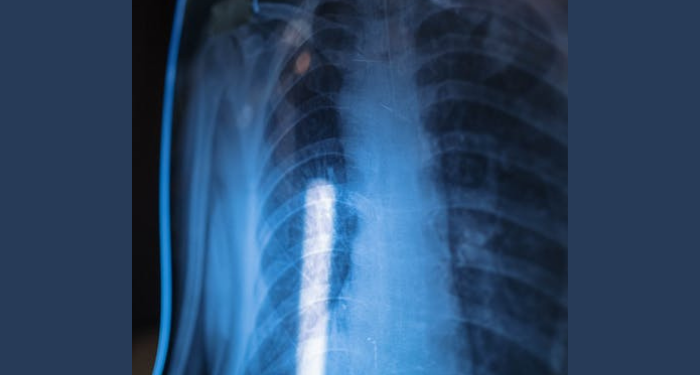

ChanelMuslim.com – Pengobatan kanker paru bisa dilakukan dengan cara-cara berikut. Mendeteksi sedini mungkin tentunya membuat kanker akan lebih cepat diatasi. Oleh sebab itu, apabila memang sudah merasakan gejalanya dan mengganggu aktivitas sehari-hari, maka tidak ada salahnya untuk diperiksa.

Dikutip dari laman primayahospital.com, berikut 8 cara pengobatan kanker paru. Sebelum itu, ada sejumlah faktor pertimbangan untuk menentukan pengobatan mana yang cocok. Contohnya, faktor jenis kanker, ukuran dan posisi kanker, stadium, dan kesehatan pasien secara keseluruhan